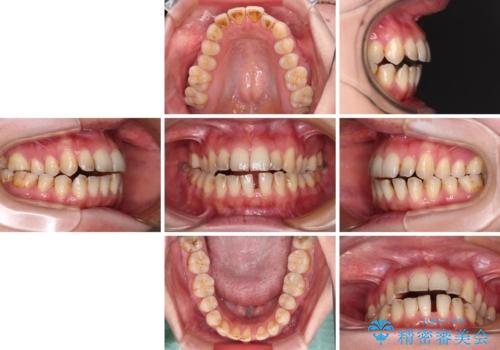

- 上下前歯の隙間を気にして来院された患者様です。

下顎前歯が1本欠損しており、上下小臼歯はクロスバイトとなり、上下前歯の接触もないという不正咬合の状態でした。

クロスバイトはワイヤー矯正が得意とするところであり、上下前歯の非接触や開咬はインビザラインの得意とするところであるので、ワイヤー装置により事前にクロスバイトを改善し、その後にインビザラインにて仕上げていくこととしました。